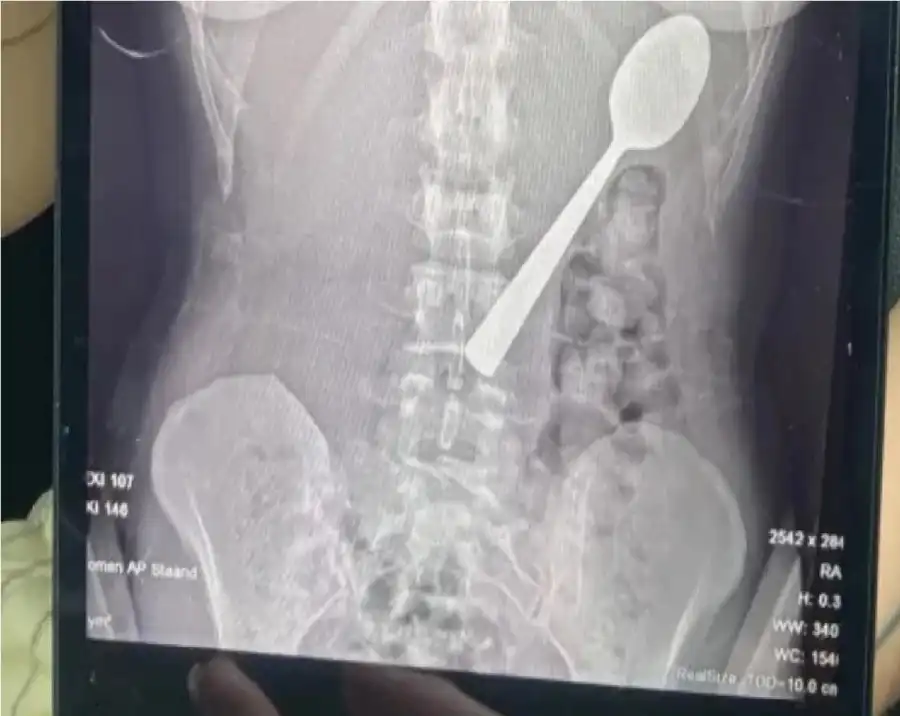

وقالت ريمي أملينكس، البالغة من العمر 28 عاماً، إنها اضطرت للاختيار بين الاختناق أو ابتلاع الملعقة، مشيرة إلى شعورها بأنها "انزلقت بسلاسة إلى معدتها".وأضافت في تصريحات صحفية أنها كانت تجلس على الأريكة أثناء تناول الزبادي، وعندما قفز كلبها من نوع "هنغاريان فيزلا" المعروف بنشاطه، تفاجأت بشكل كبير ما أدى إلى انحشار الملعقة في حلقها بالخطأ، فحاولت إزالتها بيدها، لكن الموقف كان سريعاً جداً ولم يكن أمامها سوى ابتلاعها لتجنب الاختناق.ونظراً لشعورها بالحرج، لم تخبر شريكها بما حدث فور عودته من العمل، وادّعت أن كل شيء على ما يرام.وبعد تناول العشاء، أدركت خطورة الموقف، وذهبت إلى الأطباء الذين أبلغوها أن الملعقة كبيرة جداً لتخرج طبيعياً، ما استدعى انتظار إجراء منظار معدة.وخلال هذه الفترة، شعرت المريضة بحركة الملعقة داخل جسدها، وأصيب جسدها بالانتفاخ وشعرت بالغثيان وصعوبة في النوم.وأُزيلت الملعقة بعد يومين تحت التخدير الموضعي، حيث اضطر الأطباء لتدويرها داخل المعدة، ما تسبب في نزيف بسيط، وأكدت ريمي أن الحادث لم يترك أي أضرار دائمة، لكنها تعرضت لالتهاب في الحلق ونزيف في المعدة طفيف وحساسية لبعض الوقت.ورغم التجربة المؤلمة، قررت ريمي الاحتفاظ بالملعقة كتذكار، وقالت إن شريكها يخطط لتحويلها إلى قطعة فنية فريدة من نوعها في منزلهما.بسبب 'قفزة كلب'.. بلجيكية تبتلع ملعقة طولها 17 سنتيمتراً عن طريق الخطأ